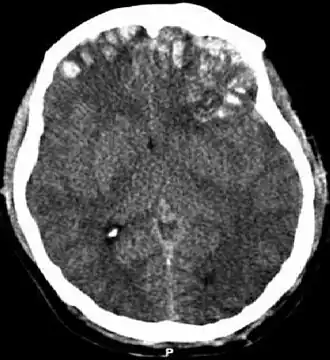

| Tomografia computadorizada mostrando contusões cerebrais, hemorragia nos hemisférios, hematoma subdural à esquerda e fraturas do crânio. | |

A contusão cerebral, do latim contusio cerebri, é uma forma de lesão cerebral traumática.[1] A contusão ocorre em 20-30% dos ferimentos graves na cabeça. A lesão pode causar um declínio na função mental a longo prazo e, no cenário de emergência, pode resultar em hérnia cerebral, uma condição com risco de vida em que partes do cérebro são pressionadas para passar por partes do crânio.[2]